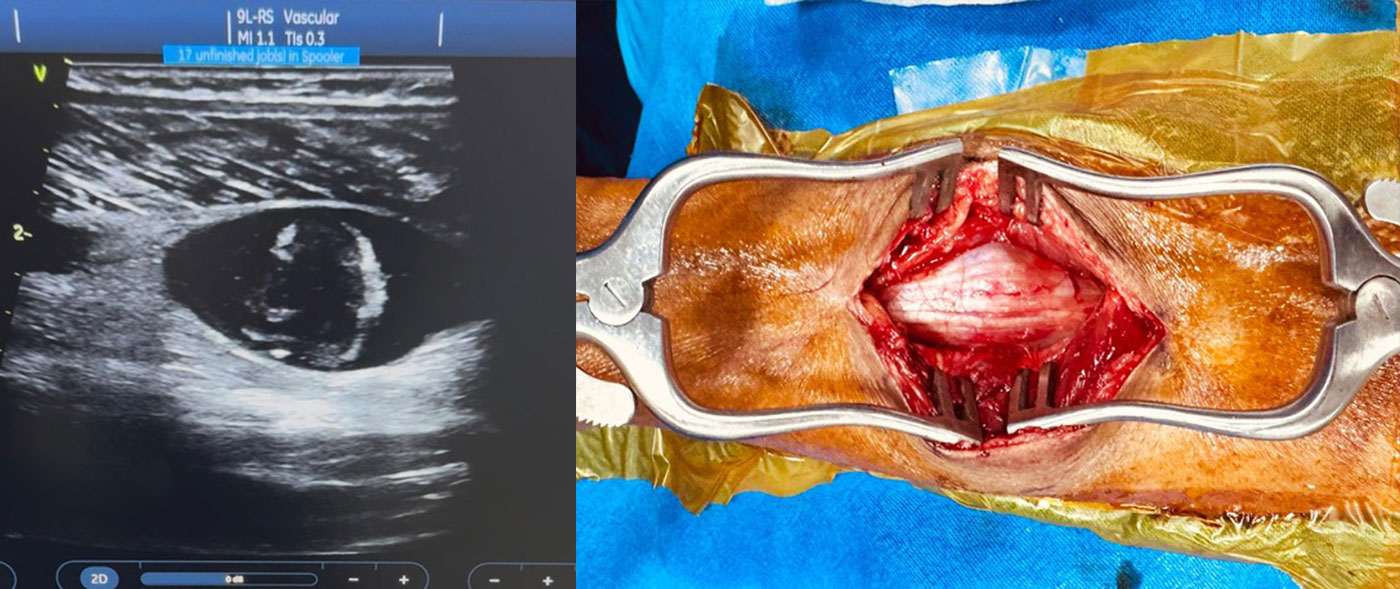

Peripheral nerve problems, such as nerve injuries, compressions like carpal tunnel syndrome, and nerve tumors, can lead to symptoms like pain, tingling, numbness, and muscle weakness. These conditions can severely affect a patient's quality of life. Surgery is often recommended when conservative treatments like medication and physiotherapy fail to provide relief, or when there's a risk of permanent nerve damage or motor weakness.

Advanced techniques in peripheral nerve surgery have significantly improved patient outcomes, offering a chance for restored function and relief from pain. Dr. Ujwal Yeole meticulously weighs the pros and cons before suggesting surgical interventions, providing patients with the best and latest treatment options.